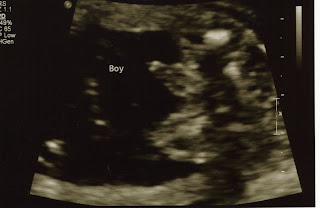

Today Tanisha was experiencing a lot of pain in her abdomen. The doctor thought it would be a good time to do an ultrasound (it was originally supposed to be 2 days later) and see what was going on. When they started looking in there, the first thing they noticed was that Aiden's head was down. This is huge news because it means he is not breach and if he comes any time soon she wont need a C-section. Then they looked at him to see how everything was doing and checked to see if there was enough amniotic fluid. There was. Then they looked at her cervix. Not only was in no longer fully dilated, but it went down to 3 centimeters! When we first came in she was 5. Lastly, they were able to see how big he was. At 23 weeks and 6 days, my son is 1 pound 12 ounces. Our doctor told us in order for them to have a reasonable chance at doing anything if he were born right now Aiden would have to be in the 90th percentile for babies his age. If you remember a few weeks ago he was in the 76th percentile. Then the last ultrasound he was in the 85th percentile. Now at 1 pound 12 ounces he's in the 96th percentile! If you think about it, that means my son is one of the biggest babies EVER! For his age. And he's been growing at an amazingly consistent accelerated pace. We are very excited to say the least. We have been praying so much, we are so glad that even if he comes earlier than we want, he's got as good of a chance of survival as he can possibly have. Thank God for that.